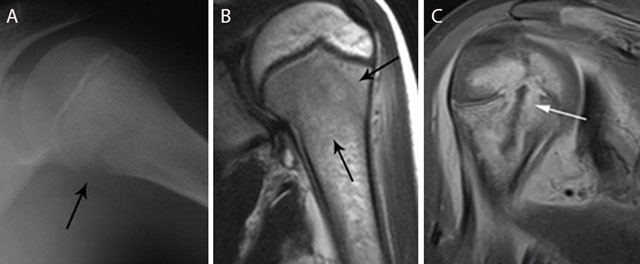

Figure 3

Acute osteomyelitis in 2 different patients. Plain radiograph (a) and coronal T2–WI (b) of acute osteomyelitis in the left proximal humerus. Another example of a child with osteomyelitis in the right proximal humerus (c) on coronal T1–WI with FS after gadolinium contrast administration. Standard radiography (a) shows a subtle osteolytic lesion at the metaphysis and loss of cortical delineation of the medial humerus (black arrow). The surrounding bone marrow edema (black arrows) (b) is restricted to the metaphysis in most cases of childhood osteomyelitis. The relativity of the barrier of the growth plate on MRI is illustrated in (c) Although a rim-enhancing intra-osseous abscess (white arrow) corresponding with the main site of infection is located at the metaphysis, there is also focal enhancement of the growth plate and epiphysis, in keeping with metaphyseal crossing.